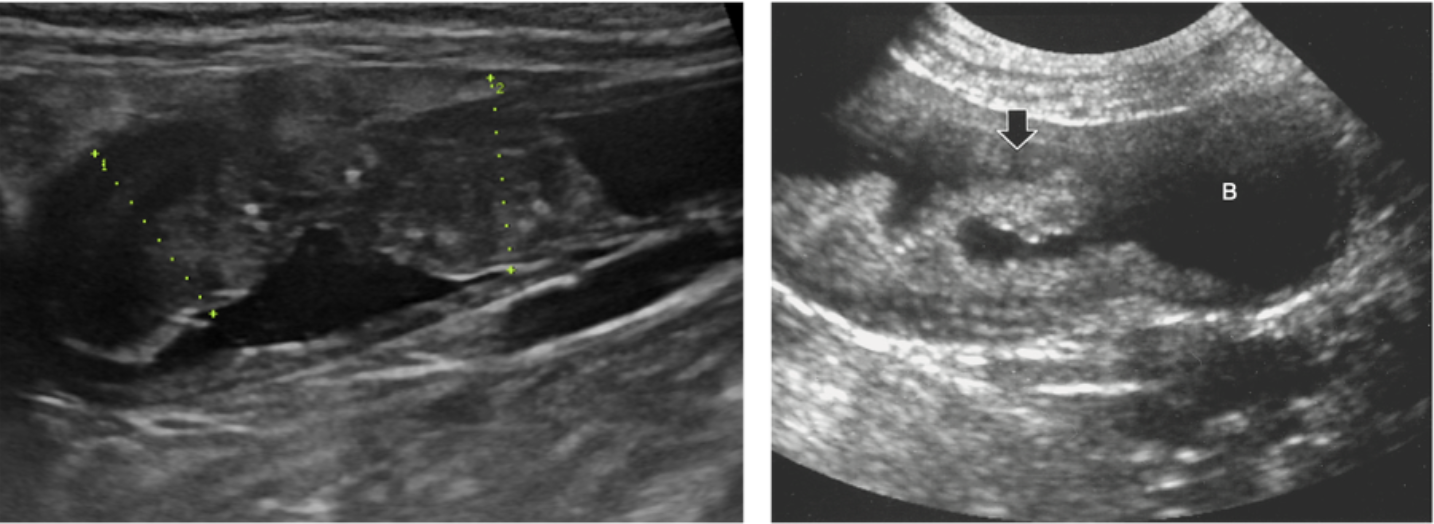

먼저, 복부초음파를 통해 방광 내 종괴 등 구조적인 변화를 확인합니다. 하지만, 만성적인 방광염에 의해 방광 점막에 용종이 형성된 용종성 방광염(polypoid cystitis)도 유사한 형태를 보여, 정확한 감별을 위해서는 자연 배뇨나 요도 카테터를 통해 채취한 소변을 이용한 추가 검사가 필요합니다.

복부초음파에서 관찰되는 방광 이행상피암종(좌)과 용종성 방광염(우) (사진=Small Animal Diagnostic Ultrasound, 4th ed)